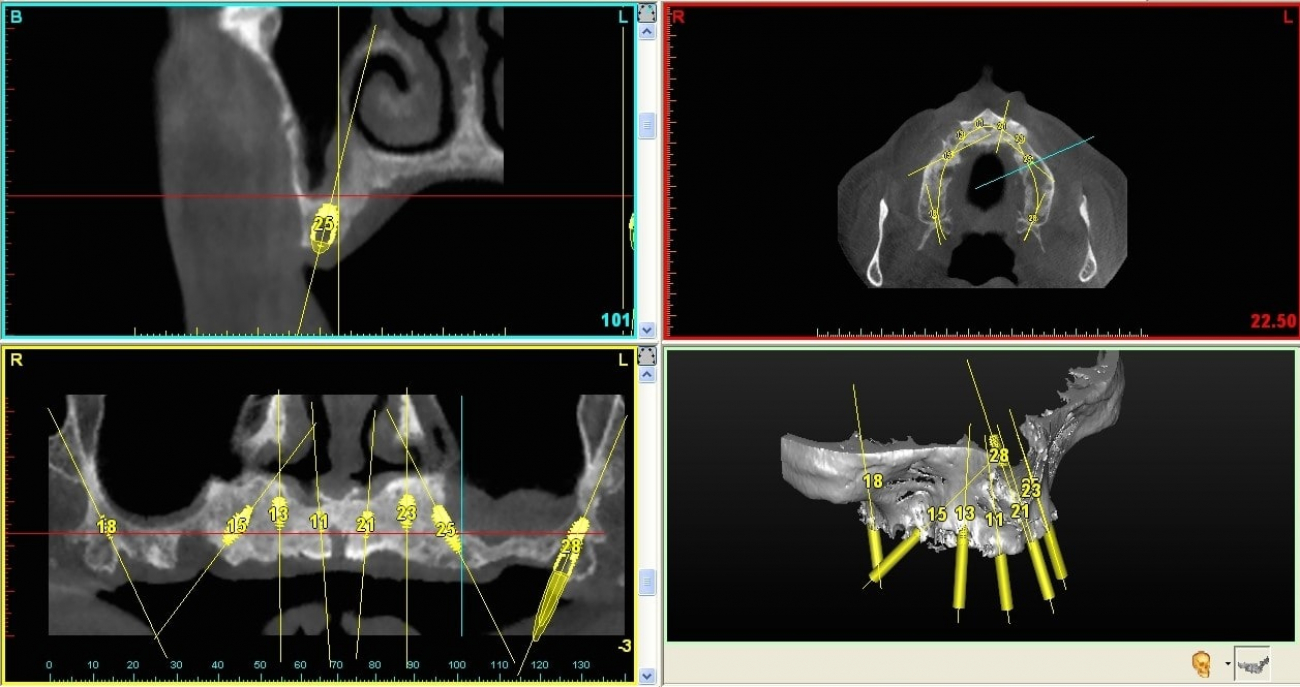

Questa metodica, grazie all’ausilio di uno specifico software che utilizza i dati ottenuti da una TAC del paziente, che viene realizzata in studio, permette di ottenere una “mascherina chirurgica” che guiderà l’odontoiatra nella disposizione degli impianti in maniera sicura, rapida e minimamente invasiva.